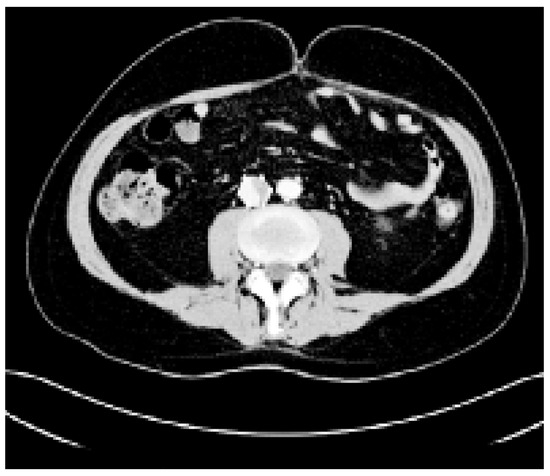

Risk Stratification of Pulmonary Embolism

by Nils Kucher

Cardiovasc. Med. 2006, 9(4), 146; https://doi.org/10.4414/cvm.2006.01169 - 28 Apr 2006

Acute pulmonary embolism (PE) is a heterogenous condition, with varying early and long term clinical outcomes. The mortality rate in PE patients is higher than in patients with acute myocardial infarction, exceeding 10% at 30 days and 16% at 3 months [1]. Within 30 days, the most common cause of death is right ventricular failure, and most deaths beyond 30 days often are due to underlying chronic conditions, including cancer, congestive heart failure, or chronic lung disease. With therapeutic levels of anticoagulation, most patients will likely have an uneventful clinical course. Some patients, however, suffer rapid clinical deterioration, including death from right ventricular failure or the need for cardiopulmonary resuscitation, mechanical ventilation, administration of pressors for systolic arterial hypotension, rescue thrombolysis, or surgical embolectomy. Contemporary PE risk stratification tools are (1.) the clinical evaluation, (2.) cardiac biomarkers, (3.) twelve-lead electrocardiography, (4.) echocardiography, and (5.) chest computed tomography. Full article